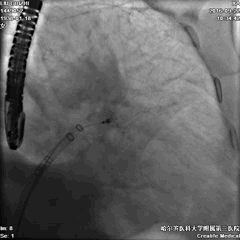

手术过程—左心耳造影选择封堵器

术中TEE双平面及DSA造影显示,梳状肌发达,延伸至心耳口部。

DSA造影显示LAA开口直径18mm,深26mm,拟采用24mm Watchman封堵器。